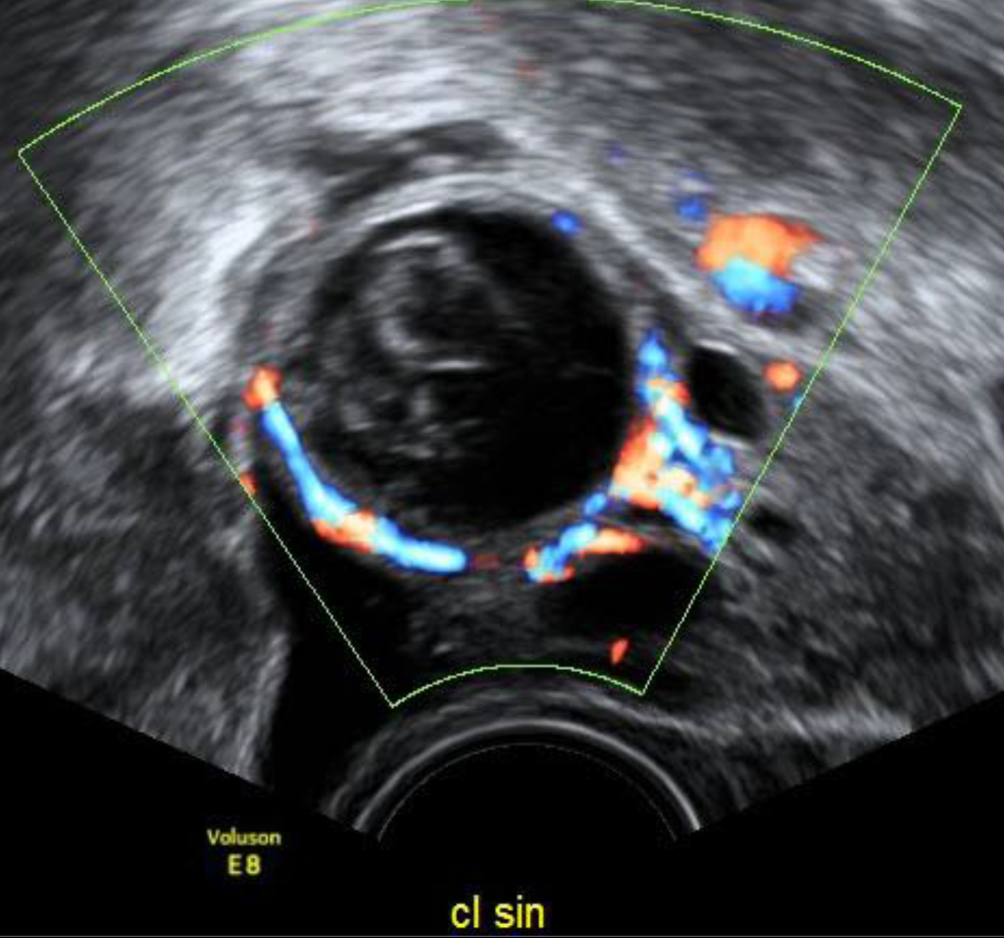

Abb. 1

Ein von Erscheinungsbild und Echodensität nicht vom restlichen Ovar zu unterscheidendes Corpus luteum zeigt sich im Farbdoppler durch die markante zirkuläre Vaskularisation, den „ring of fire“

Das Corpus luteum unterscheidet sich nicht vom Ovarparenchym, erst wenn man den Farbdoppler aktiviert, zeigt sich ein zirkulärer „ring of fire“ (Abb. 1).

Sehr hilfreich ist der Farbdoppler bei der Feststellung eines Corpus luteum – die für die endokrine Aktivität des Organs nötige periphere Vaskularisation zeigt sich in einer meist kreisrunden, 1–2 cm großen charakteristischen Struktur im Ovar – im Ultraschalljargon, seit es den Farbdoppler gibt, als „ring of fire“ bekannt. Diese Vaskularisation nimmt rund 10 Tage nach der Ovulation ab, mit Beginn der Monatsblutung ist sie kaum mehr vorhanden. Solide Strukturen im Inneren der Flüssigkeit kann man nur dann sicher als Koagel beschreiben, wenn sie im Farbdoppler nicht vaskularisiert sind. Wären die echodensen Strukturen innerhalb der Flüssigkeit in Abb. 4 vaskularisiert, müsste die Verdachtsdiagnose auf ein Muzinkystom oder ein Malignom lauten und der Befund müsste nach den IOTA-Kriterien beurteilt werden [1].